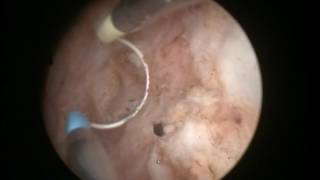

TURis Plasma Vaporization εξάχνωση προστάτη Δρ. Κυμηνάς Laser λιθοθρυψία με εύκαμπτο ουρηρτηροσκόπιο Εξελκυσμός λίθου ουρητήρα Διουρηθρική όγκου ουροδόχου κύστεως 1 www.kyminas-urology.gr Διουρηθρική προστατεκτομή TURis Δρ. Κυμηνάς Ευάγγελος www.kyminas-urology.gr TUR-P Διουρηθρική προστατεκτομή TURis 1 Δρ. Κυμηνάς Ευάγγελος www.kyminas-urology.gr Laser λιθοθρυψία λίθου ουρητήρα Δρ. Κυμηνάς Ευάγγελος www.kyminas-urology.gr ουρητηροσκόπηση καρκίνος ουρητήρα Δρ. Κυμηνάς Ευάγγελος www.kyminas-urology.gr Ουρητηροκήλη Δρ. Κυμηνάς Ευάγγελος www.kyminas-urology.gr Διουρηθρική θηλώματος κύστεως υψηλού βαθμού κακοήθειας Kyminas-urology.gr